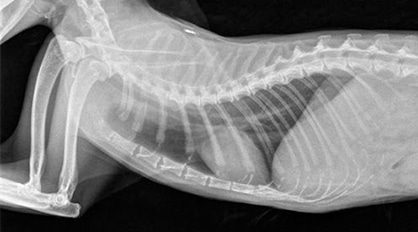

Radiographs (X-rays) are an important diagnostic tool used for your pets. Our Medowie clinic is equipped with a state-of-the-art X-ray machine that can produce excellent quality images for all animals big and small.

After a complete physical examination of your pet, our veterinarians can determine if your pet requires radiographs.

Our patients will be admitted into our hospital for the day for the radiographs to be taken. We ask that you bring your pet unfed in the morning as they may require sedation or anaesthesia to allow us to obtain the best quality radiographs as possible.

Once the radiographs have been taken we will give you a call or book an appointment for our veterinarians to discuss the diagnosis and our recommended treatment plan for your pet.